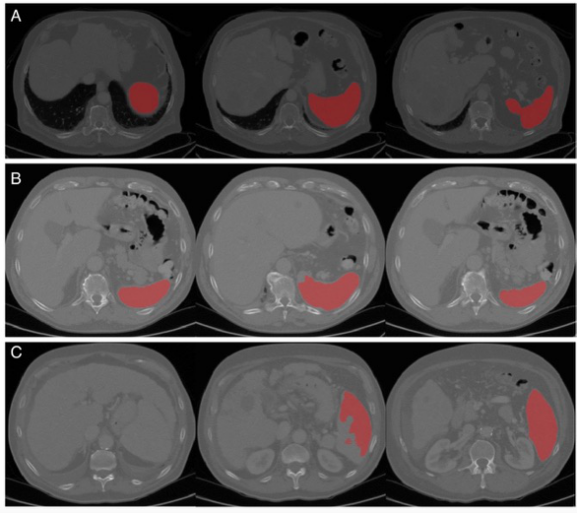

圖 算法性能的代表性圖像(從左到右是脾臟上部、中部和下部的圖像)。A完美的分割,B可接受的分割(中間有輕微的分割錯誤),C差的分割(上部有主要的分割錯誤,有吻合的肝臟和脾臟現(xiàn)象)